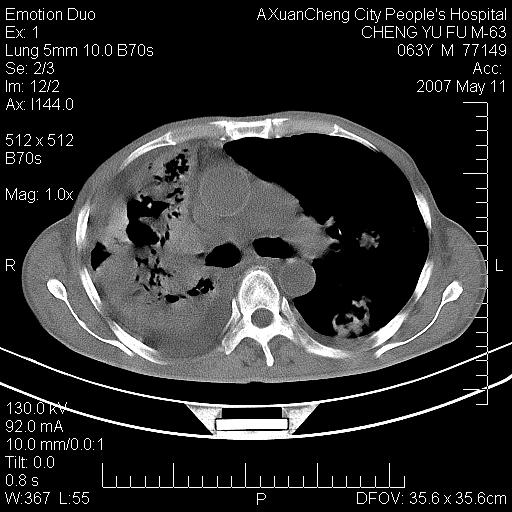

以下是引用小初学者在2007-5-11 19:32:00的发言:[br]1、首先考虑干酪性肺炎支气管播散[br]2、支气管肺泡癌待排

以下是引用zhangzhongshou在2007-5-11 19:30:00的发言:[br]细支气管肺泡癌可能性大。